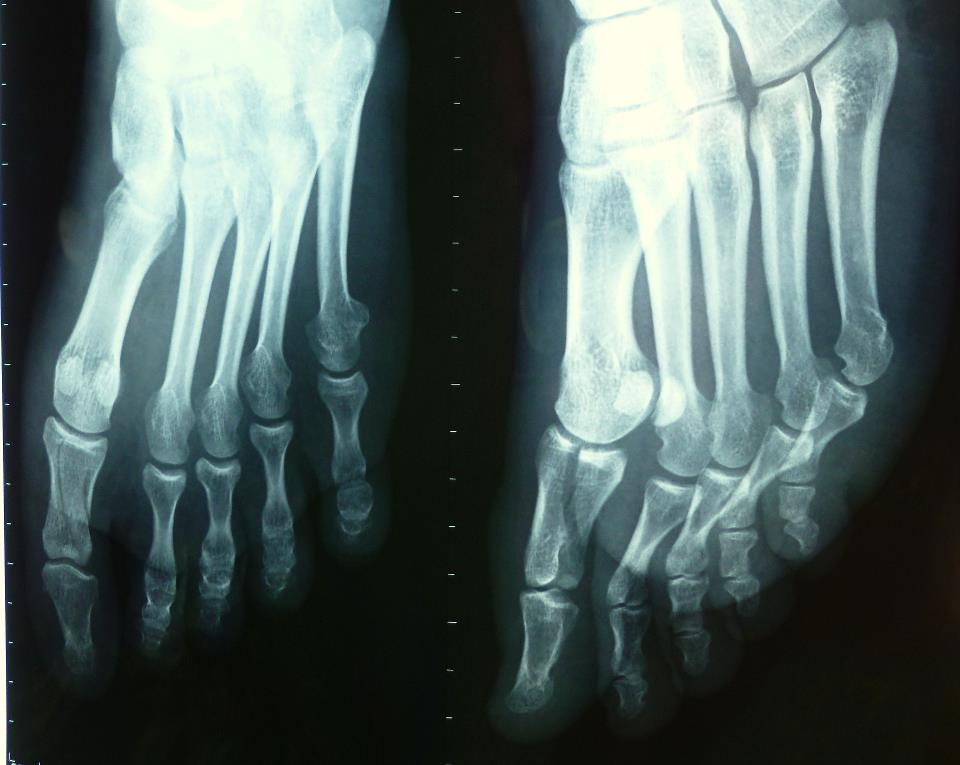

Ik kreeg mn eigen rolstoel (best vet, stiekem - vooral als je niet door de suster word rondgereden, maar zelf rolt), en direct naar de rontgen afdeling. Ik heb de beste rontgenfoto jongen in de tussentijd nog een paar tips gegeven om straling te verminderen, en na een aantal minuten kregen we de fotos in handen, om terug naar de eerste hulp te nemen. Instelling technisch niet helemaal perfect, maar goed genoeg om wat duidelijke veranderingen te zien: tijdens het teruggaan naar eh hoorde ik carola zeggen "nou, die enkel is dus stuk" en met een snelle blik achterover vanuit de rolstoel was ik het daar wel mee eens. Hetzelfde met de grote teen.

Ik wist nog wel een echt goede orthopeed in Jakarta, die ook 1 van de orangutans heeft gefixt vorig jaar. Die had ongeveer een milliseconde nodig om de breuken te zien, en gaf de keuze opereren (pennetje erin, en meteen klaar) of, iets langere duur, maar zelfde resultaat, want nette fractuurlijn - een gipsje. Het is dus de tweede keus geworden, 2 weken rust, en dan nog 2-4 weken langer dat gips erop laten, maar mag er dan op lopen.